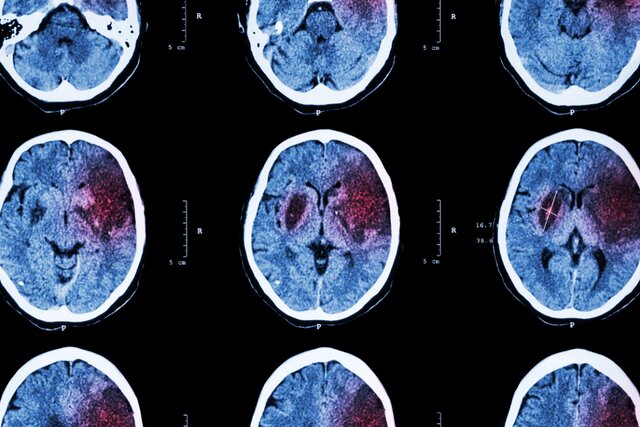

ایسنا نوشت؛ «بررسی آثار پیش‌درمانی بالقوه حاصل از تجویز miRNA-149-5p بر بهبود نقص‌های نورولوژیک در مدل سکته مغزی رت» عنوان طرحی است که در قالب رساله دکتری محمدرضا بیگدلی مسئول آن بوده و  سمیرا وحیدی با حمایت بنیاد ملی علم ایران به پایان رسانده است. بیگدلی با مدرک دکتری تخصصی فیزیولوژی از دانشگاه تربیت مدرس درباره این طرح توضیح داد: سکته مغزی به‌عنوان شایع‌ترین بیماری عروق مغزی و معضل اولیه سلامت عمومی شناخته می شود که با شیوع و مرگ‌ومیر بالا، شروع حاد، رشد سریع و پیامدهای شدید شناخته می‌شود و متأسفانه میزان بروز آن در حال افزایش است.

وی ادامه داد: سکته مغزی دومین عامل مرگ‌ومیر و علت اصلی ناتوانی جسمی است. هر سال تقریباً 15 میلیون نفر دچار سکته مغزی می‌شوند و حدود 5 میلیون نفر در سراسر جهان فوت می‌کنند. با توجه به آسیب‌شناسی زمینه‌ای، سکته مغزی ممکن است به عنوان سکته مغزی ایسکمیک یا هموراژیک طبقه‌بندی شود.

این محقق و پژوهشگر تصریح کرد: 85‌درصد کل سکته‌ها، سکته مغزی ایسکمیک است، درحالی‌که سکته مغزی هموراژیک علت 15 درصد از سکته‌ها است. اخیراً، پیشرفت چشمگیری در درک مکانیسم‌های پاتوفیزیولوژی سکته مغزی، به ویژه در سکته مغزی ایسکمیک صورت گرفته است.